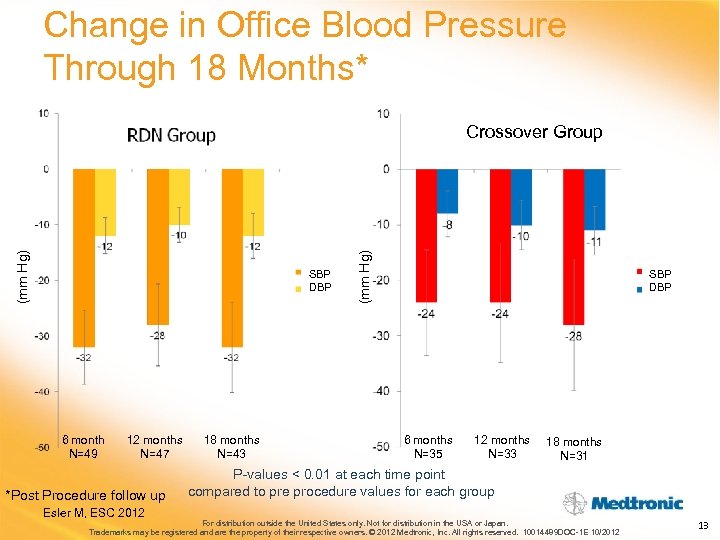

Change in Office Blood Pressure Through 18 Months* SBP DBP 6 month N=49 12 months N=47 *Post Procedure follow up Esler M, ESC 2012 18 months N=43 (mm Hg) Crossover Group SBP DBP 6 months N=35 12 months N=33 18 months N=31 P-values < 0. 01 at each time point compared to pre procedure values for each group For distribution outside the United States only. Not for distribution in the USA or Japan. Trademarks may be registered and are the property of their respective owners. © 2012 Medtronic, Inc. All rights reserved. 10014489 DOC-1 E 10/2012 13

Change in Office Blood Pressure Through 18 Months* SBP DBP 6 month N=49 12 months N=47 *Post Procedure follow up Esler M, ESC 2012 18 months N=43 (mm Hg) Crossover Group SBP DBP 6 months N=35 12 months N=33 18 months N=31 P-values < 0. 01 at each time point compared to pre procedure values for each group For distribution outside the United States only. Not for distribution in the USA or Japan. Trademarks may be registered and are the property of their respective owners. © 2012 Medtronic, Inc. All rights reserved. 10014489 DOC-1 E 10/2012 13